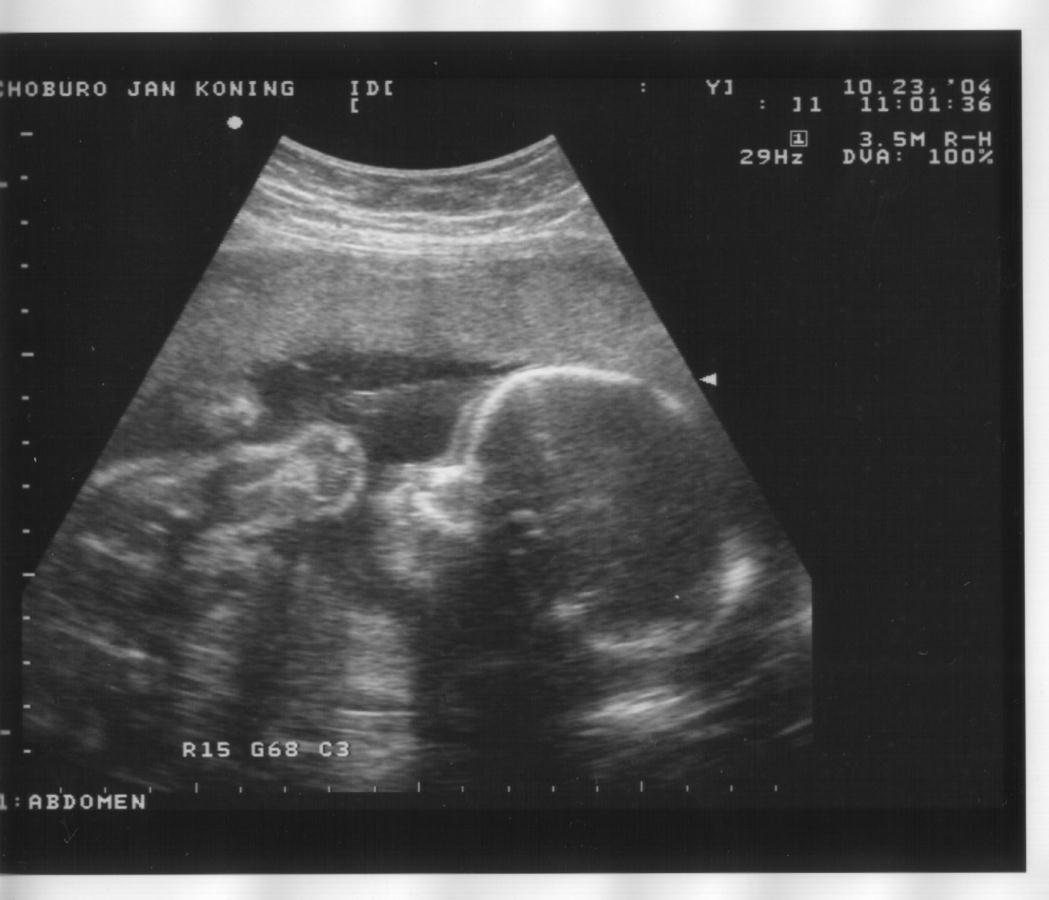

23 oktober 2004

Zijaanzicht hoofd, handje bij het gezicht en oog, bovenste helft borst, opgetrokken knietjes